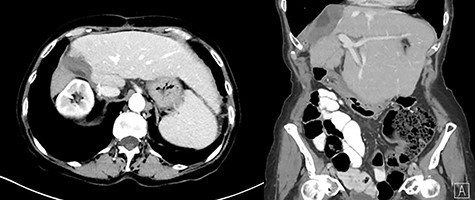

In 2018, the patient had a low dose chest CT for lung cancer screening, given her prior smoking history. The chest CT demonstrated a mass along the right hepatic dome. Triple-phase contrast-enhanced (ce) CT of the abdomen subsequently revealed a large multi-lobulated low-attenuation mass in the right hepatic lobe, predominantly involving Segments V and VIII and, to a lesser extent, Segments VI and VII, measuring 8.8 × 8.3 × 8.2 cm, and associated with a satellite lesion in Segment IVA, measuring 2.2 cm (Fig. 1). A PET CT was ordered and was negative for extrahepatic neoplastic disease.

Abdominal ceCT demonstrated an arterially enhancing mass with early washout characteristic of HCC; venous phase axial and coronal images are featured.